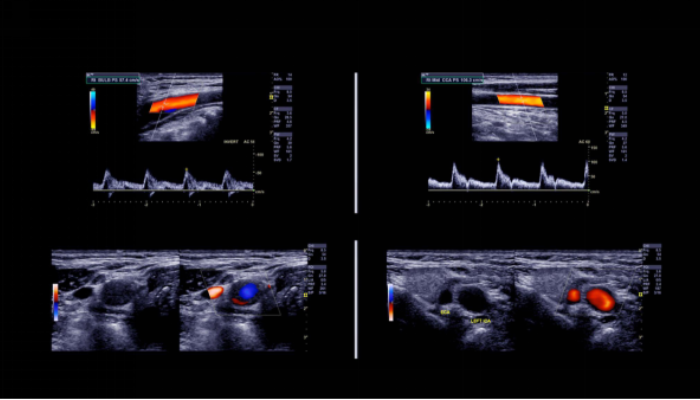

O doppler arterial e venoso é um exame não invasivo que utiliza da tecnologia de ultrassom aliado à função doppler, para ajudar a identificar com precisão doenças do sistema vascular.

Também chamado de ecodoppler, a análise gera imagens coloridas de alta resolução, possibilitando visualizar o movimento do sangue nas veias e artérias em tempo real.

Permite estimar o fluxo de sangue nos vasos sanguíneos de praticamente todas as regiões do corpo.